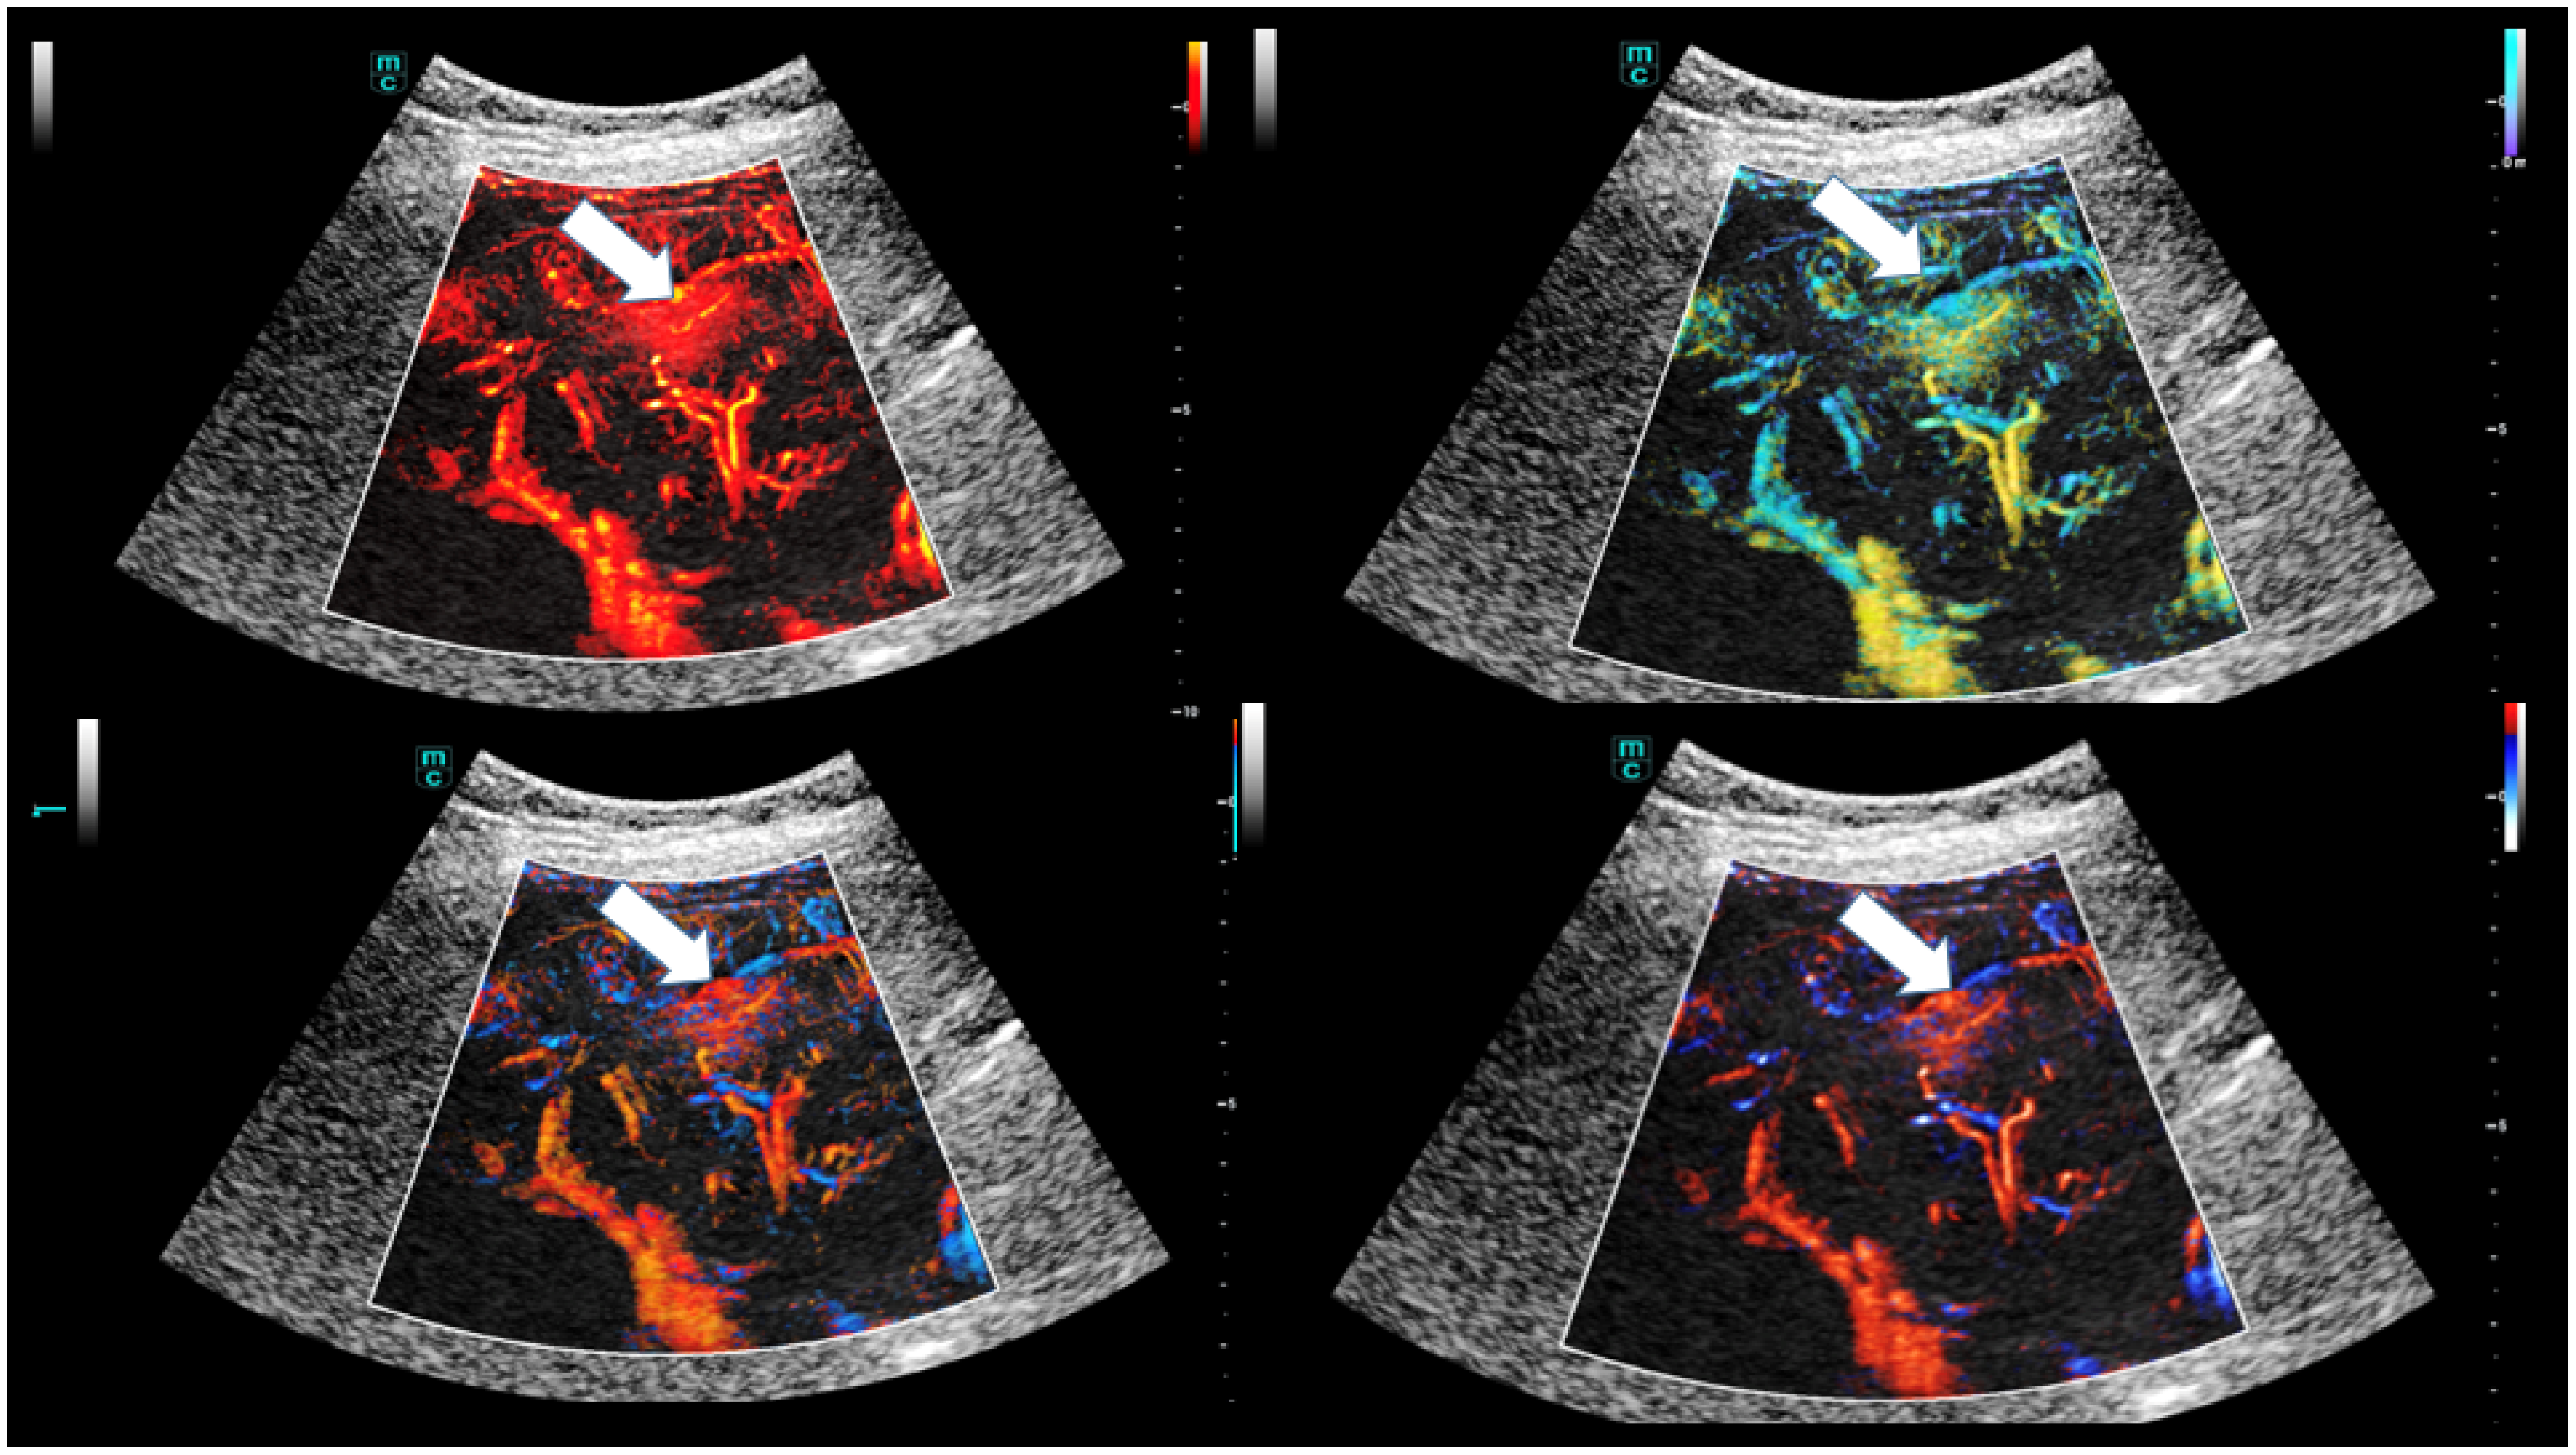

- Dropco, I.; Kaiser, U.; Wagner, L.; Brunner, S.M.; Schlitt, H.J.; Stroszcynski, C.; Jung, F.; Yi, D.; Herr, W.; Jung, E.M. Color Mapping using Ultrasound System-integrated Perfusion Software for Evaluation of Focal Liver Lesions: A Possible First Step for More Independent Reading. J. Gastrointestin. Liver Dis. 2023, 32, 479–486. [Google Scholar] [CrossRef]